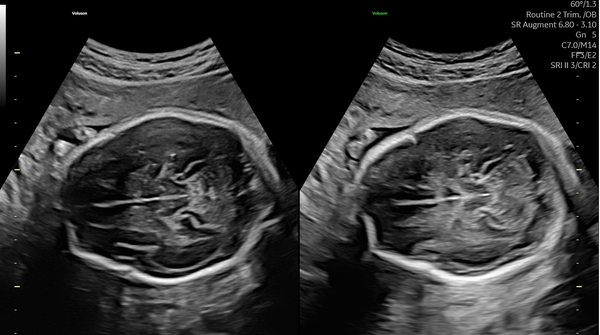

減衰を補うAugmentと,音響陰影を補うShadow Reductionを使用した画像(off/on)